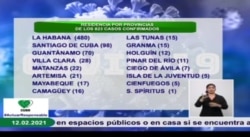

Cuba reportó este viernes otros 4 fallecidos por COVID-19 y 823 nuevos casos de la enfermedad, una cifra “discretamente inferior” de contagios, pero “todavía muy alta”, según dijo en su conferencia de prensa diaria el jefe de Epidemiología del Ministerio de Salud Pública (MINSAP).

La isla alcanza ya los 36,595 casos de coronavirus y 257 muertes desde que comenzó la pandemia. La tasa de incidencia de la enfermedad en el país por cada 100,000 habitantes es de 108.

En La Habana, centro de la pandemia en la isla, y con 480 casos reportados en el día, se controlan 1,315 focos de transmisión, el mayor número en los municipios Diez de Octubre (164), Arroyo Naranjo (126, de ellos tres con más de cinco casos), Boyeros (109, de ellos tres con más de cinco casos) y Marianao (105), reportó el diario estatal Tribuna de La Habana.